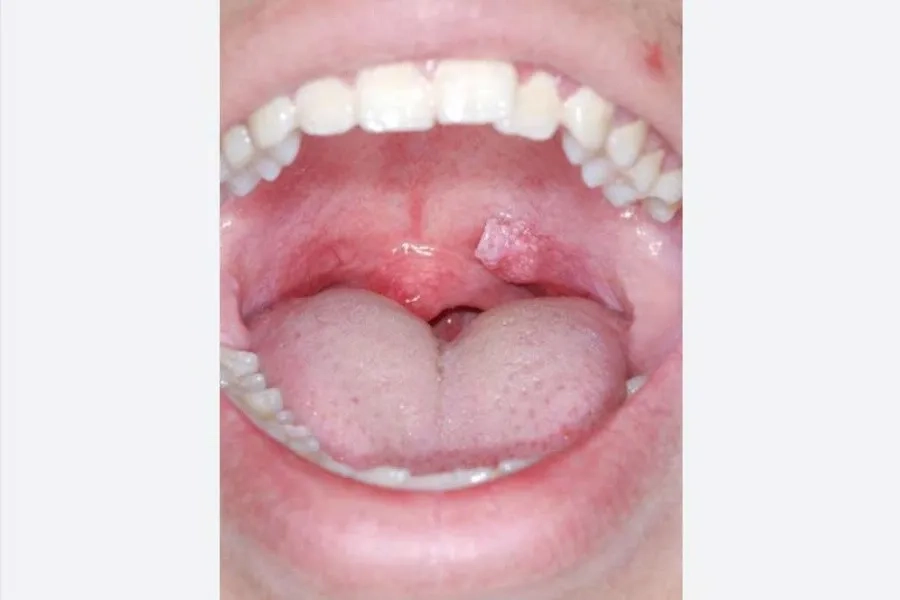

Mụn cóc sinh dục (sùi mào gà) có thể xuất hiện ở miệng, cơ quan sinh dục

- Mụn cóc hoặc u nhú trong miệng: xuất hiện ở lưỡi, lợi, vòm họng, amidan hoặc mặt trong má, thường có màu trắng, hồng hoặc hơi đỏ.

- Xuất hiện u nhú hoặc mụn cóc ở vùng họng, amidan hoặc lưỡi gà: thường nhỏ, màu trắng, hồng hoặc đỏ.

Virus HPV có thể gây mụn cóc sinh dục xuất hiện ở vùng hầu họng